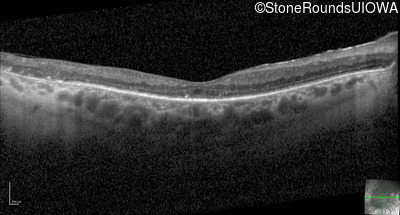

Optical Coherence Tomography - Right - 20/150

Exemplar / OCT Stack

OCT Stack